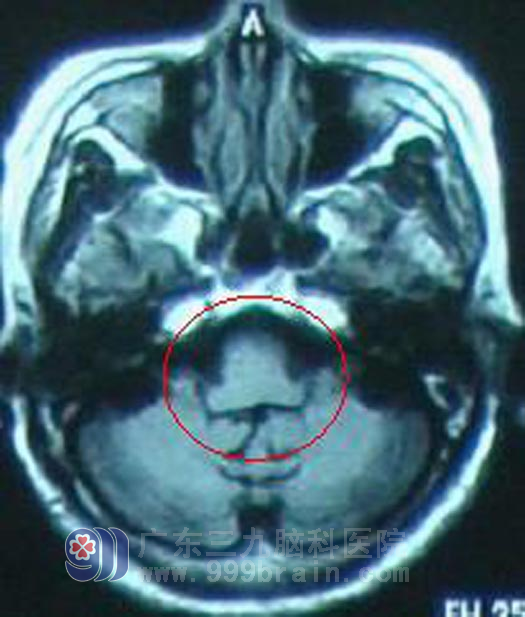

李阿姨及家属选择直接放疗。治疗过程中,患者说话不清症状逐渐好转,左侧肢体肌力在放疗及康复理疗的综合作用下逐渐恢复正常。至放疗50Gy结束后,患者一般情况良好,言语正常,病理征未引出。http://www.999brain.com/

治疗结束后定期复查,未见肿瘤复发征象,在家还可以做家务,照顾孙子,患者未出现不适,目前随访8年余,一般情况良好。http://www.999brain.com/

放疗后8年